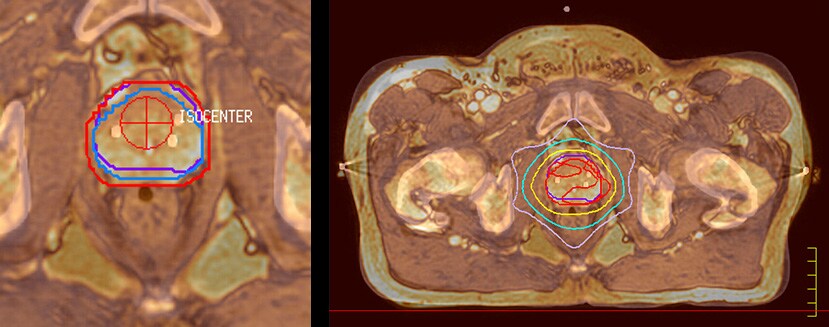

• Ingenia MR-RT XD image serie

MR-only radiotherapy planning

Experience the true potential and drive impact with MR-only radiotherapy planning.